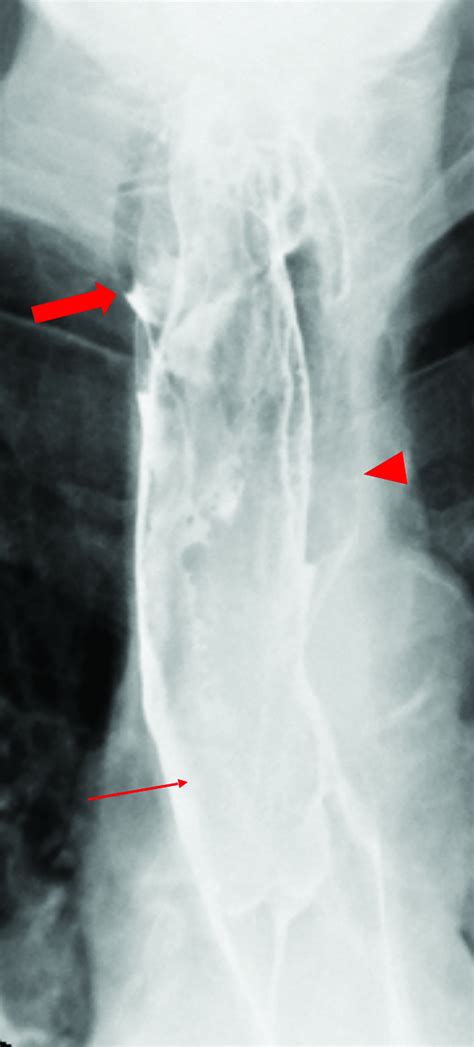

Barium Swallow X-ray imaging to see how the esophagus functions and if a mass is obstructing flow.

Endoscopic Ultrasound (EUS) Provides detailed images of the layers of the esophageal wall to determine the depth of the polyp.